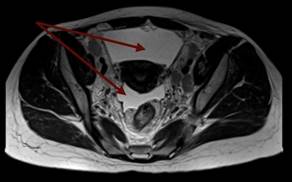

В дальнейшем была проведена МРТ органов малого таза с внутривенным контрастированием (рис. 3а, 3б). Было выявлено большое количество свободной жидкости, по задней поверхности брюшины и в пузырно-маточном углублении справа 2 узловых образования (канцероматоз), увеличенные лимфатические узлы во всех группах. Метастатические поражения костей таза.

Рис. 3а. Магнитно-резонансная томограмма органов малого таза с внутривенным контрастированием пациентки с раком желудка: метастатические поражения костей таза (1)

Рис. 3б. Магнитно-резонансная томограмма органов малого таза с внутривенным контрастированием пациентки с раком желудка: скопление свободной жидкости в малом тазу (1)